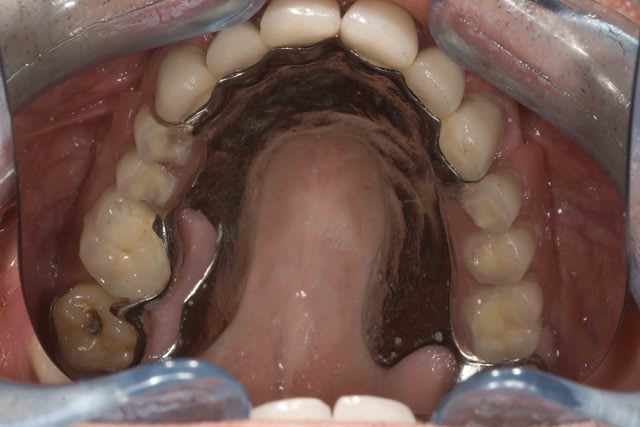

Pour le decolletage : A titre personel j'ai remarqué que si une prothése était ajouré il y avait moins de retention alimentaires et moins de caries. Donc des que je peux decolleter autour de dents naturelles je le fait . Il s'agit d'obervation personelles et non pas détudes !

pourquoi avoir choisi de décolleter au niveau de 16-17?

J'avais oublié la pano de départ + la photo des fraisages et attachement .